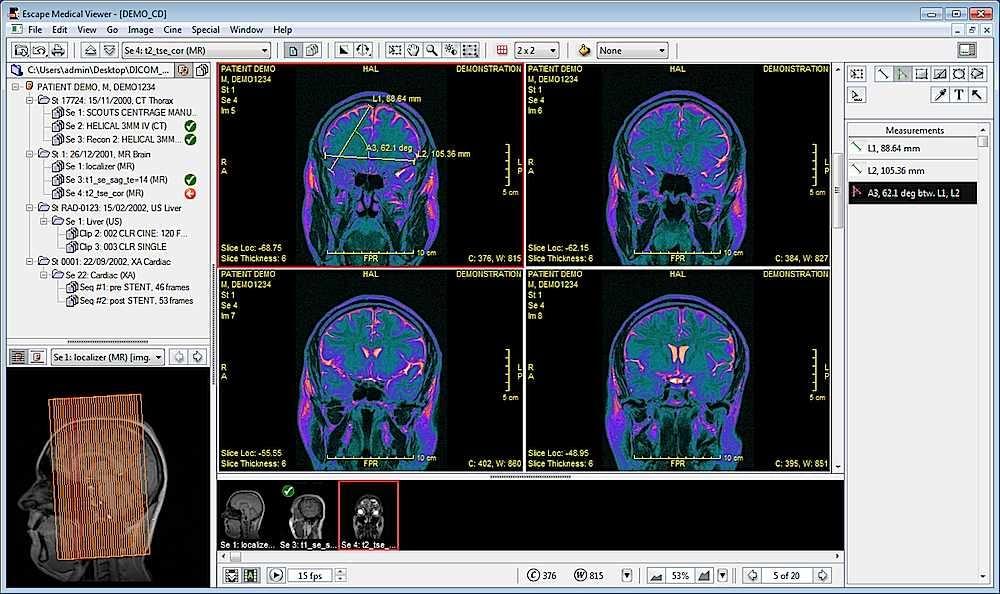

Лазерная камера для печати медицинских изображений на пленке стандарт dicom